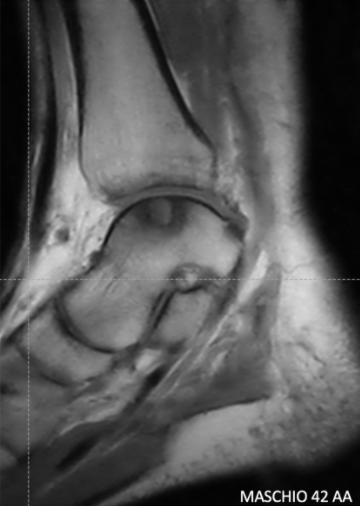

MRI of Osteochondral Lesion of the Medial Talus